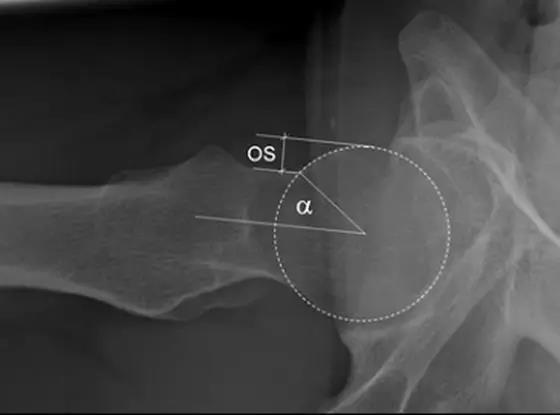

- 股骨头中心O点为圆心,股骨头正常最大半径为r,从股骨头颈连接处骨质与这个圆的交点(A点)到股骨头中心点作直线OA,此直线与股骨颈中轴线OB的交角为α角。

- 反映股骨颈骨赘突出程度,α角越大,越容易发生前上方股骨头颈与髋臼唇的撞击。

- FAI组中该角平均为74.0°±5.4°,正常对照组为42.0°±2.2°。

- α角>50°是诊断FAI的临界值。